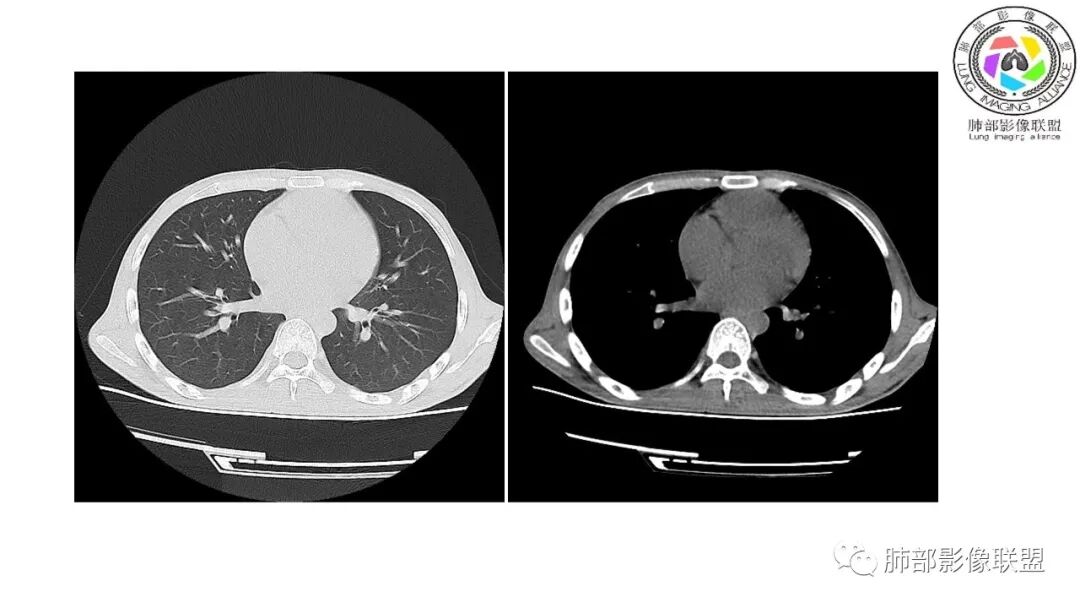

影像与临床:1.青年男性,HlV阳性,颜面部皮疹(未提供皮疹图像)、发热(高热),实验室CRP、PCT高,T-Spot阴性。2.右肺下叶空洞结节,壁厚不均,边界清楚,其内线状影,未见液平及钙化,未见卫星灶,纵隔淋巴结增大,双侧腋窝见增大淋巴结。心腔内低密度提示贫血可能。肝脾影增大,未见结节影及块影。腹膜后见多发增大淋巴结。

综合分析:本例肺部影像学改变并不具有特征性,空洞性病灶须与多种疾病鉴别,但年轻HIV阳性患者,高热,皮疹,肝脾增大,纵隔、腋窝、腹膜后见多发增大淋巴结等都强烈提示马尔尼菲篮状菌感染的可能性。